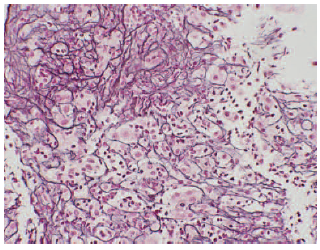

Over the next 48 hours, her liver function worsened with laboratory results showing AST 2438 IU/L, ALT 2748 IU/L, total bilirubin 12.6 mg/dL, and an international normalized ratio of 1.7. Work-up results for the cause of liver failure including anti-hepatitis A virus IgM, hepatitis B core antibody, anti-hepatitis B core IgM, anti-hepatitis C virus, anti-hepatitis E virus IgM, anti-cytomegalovirus IgM, anti-Epstein-Barr virus IgM, and anti-herpes simplex virus IgM were nonreactive. Antinuclear, anti-mitochondrial, and anti-smooth muscle antibodies were negative, and ceruloplasmin was within normal limits. Duplex sonography showed no abnormality of hepatic vascular inflow and outflow. A transjugular liver biopsy was performed on day 3 (Figure 3) revealing severe acute hepatitis with areas of confluent necrosis, scattered eosinophils, and no plasma cell infiltrates.